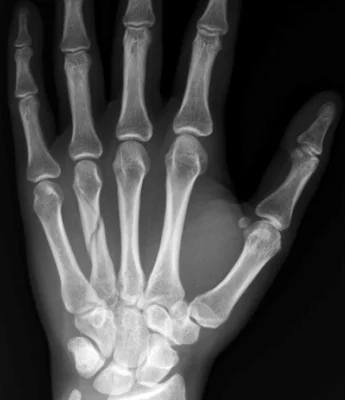

- Careful about rotational malalignment

- Check rotation by flexing the fingers